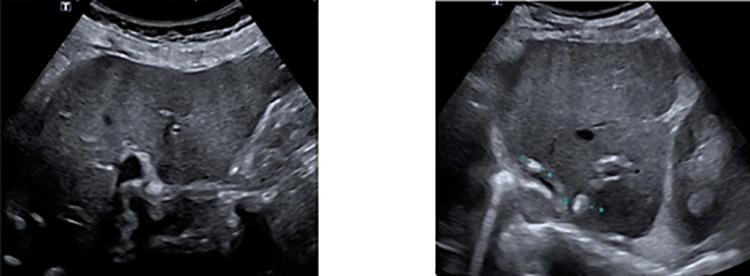

Metastases of colorectal carcinoma (CRC) in the testis are very rare and indicate an advanced stage of disease. In this case report, we present a patient with adenocarcinoma in the sigmoid colon with metastasis in the right testis. Testicular metastasis of CRC is mostly diagnosed late because of their low incidence rate. Patients with CRC and testicular metastasis have a poor prognosis. In this case, the patient turned out to have peritoneal metastasis and one should be aware that testicular metastasis could be the first sign of widespread disease.

结直肠癌(CRC)转移至睾丸非常罕见,提示疾病已处于晚期。在本病例报告中,我们呈现了一名患有乙状结肠癌并伴有右侧睾丸转移的患者。由于结直肠癌睾丸转移的发生率较低,其大多在晚期才被诊断出来。患有结直肠癌并伴有睾丸转移的患者预后较差。在本病例中,该患者最终被发现有腹膜转移,应意识到睾丸转移可能是广泛疾病的首个迹象。